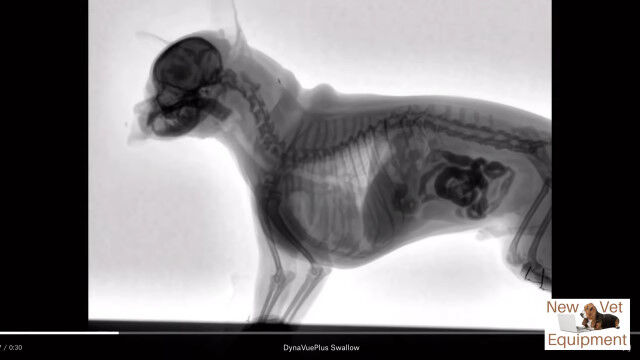

動物用レントゲンシステム、ダイナビューを用いて撮影された、犬がエサを食べる最中の体内の様子。

口から食道を通り、ゆっくり胃袋へ流れ込む様子が動画ではっきり確認できる。

Youtubeの概要欄に記載がなくて分からなかったけど、これ犬種はなんだろうね。

Veterinary Fluoroscopy - Watch the Swallow!